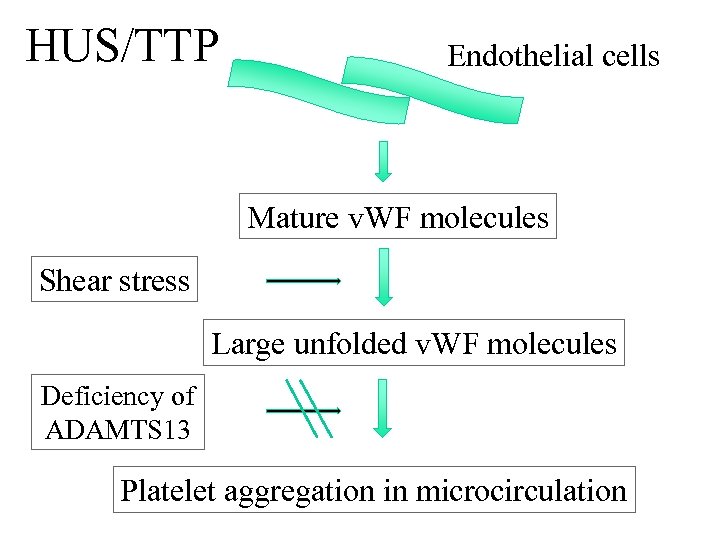

HUS/TTP • Aetiology • D+ verotoxin producing strain of E coli 0157 esp in children • D- sporadic form more commonly seen in adults. May be idiopathic or assoc with drugs, HIV and malignancy (infective diarrhoea not invariably associated) • Pathogenesis • ADAMTS 13 is a metalloproteinase which cleaves VWF to smaller subunits. Absence of or antibodies to this enzyme leads to build up of VWF multimers which promote platelet aggregation triggering MAHA • Presentation • Triad of ARF with MAHA and thrombocytopenia (HUS)

HUS/TTP • Aetiology • D+ verotoxin producing strain of E coli 0157 esp in children • D- sporadic form more commonly seen in adults. May be idiopathic or assoc with drugs, HIV and malignancy (infective diarrhoea not invariably associated) • Pathogenesis • ADAMTS 13 is a metalloproteinase which cleaves VWF to smaller subunits. Absence of or antibodies to this enzyme leads to build up of VWF multimers which promote platelet aggregation triggering MAHA • Presentation • Triad of ARF with MAHA and thrombocytopenia (HUS)

HUS/TTP Endothelial cells Mature v. WF molecules Shear stress Large unfolded v. WF molecules Deficiency of ADAMTS 13 Platelet aggregation in microcirculation

HUS/TTP Endothelial cells Mature v. WF molecules Shear stress Large unfolded v. WF molecules Deficiency of ADAMTS 13 Platelet aggregation in microcirculation